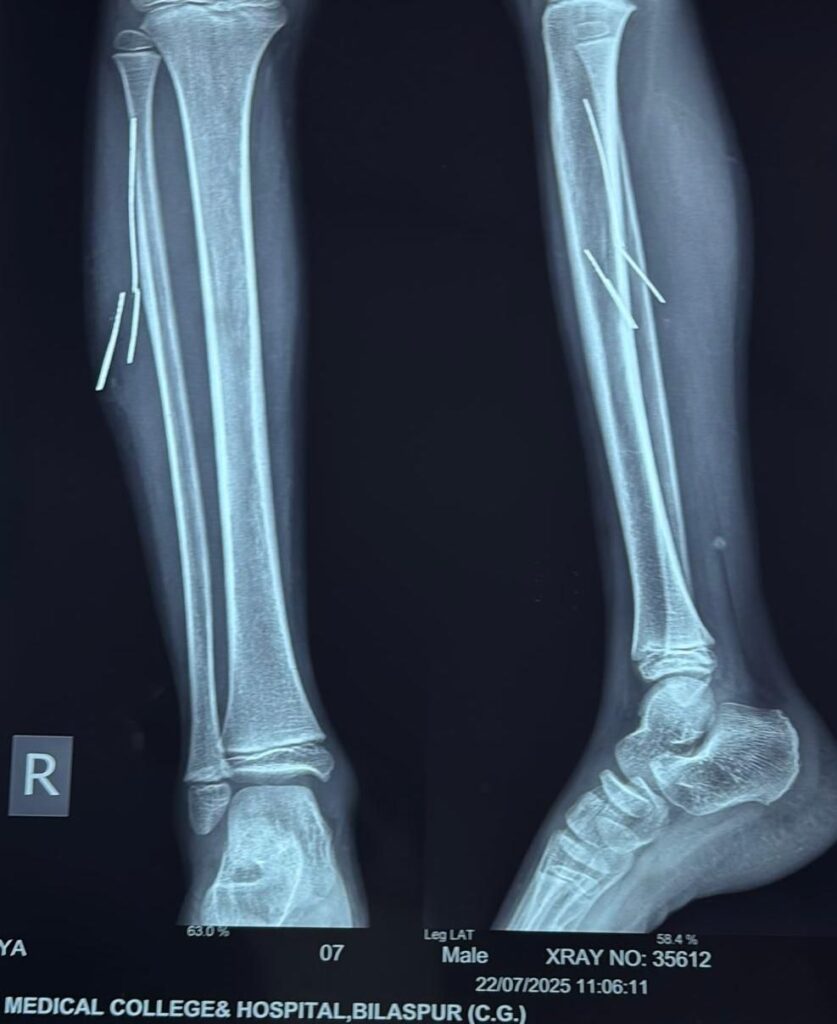

लमेर निवासी 10 वर्षीय आदित्य खांडे पिता दीप कुमार लगभग चार माह पूर्व साइकिल चलाते समय दुर्घटनाग्रस्त हो गया था। हादसे में साइकिल का टायर फटने से बाहर निकला लोहे का तार उसके दाहिने पैर में घुस गया। तार पैर में टूटकर अंदर फंस गया और चार टुकड़ों में लगभग 2 से 5 सेमी लंबाई में मांसपेशियों में धंस गया। इसके बाद बच्चे को लगातार सूजन और दर्द की शिकायत बनी रही।

तीन दिन पूर्व परिजन उसे सिम्स के सर्जरी विभाग में लेकर पहुंचे, जहां सर्जन डॉ. बी.डी. तिवारी ने जाँच करवाई। एक्सरे और सोनोग्राफी से यह पुष्टि हुई कि तार पैर की मांसपेशियों में गहराई तक धंसा हुआ है, और अंदर ही अंदर मवाद बन चुका है।

स्थिति की गंभीरता को देखते हुए डॉ. ओ.पी. राज एवं डॉ. बी.डी. तिवारी ने ऑपरेशन का निर्णय लिया। परंतु ऑपरेशन के दौरान चीरफाड़ को न्यूनतम रखने और तारों की सटीक जगह जानने के लिए रेडियोलॉजी विभाग की मदद ली गई। विभागाध्यक्ष डॉ. अर्चना सिंह के निर्देशन में असिस्टेंट प्रोफेसर डॉ. अमन अग्रवाल ने ऑपरेशन थिएटर में ही लाइव सोनोग्राफी के माध्यम से लोहे के तारों की सटीक स्थिति चिन्हित की। इसके आधार पर सर्जनों ने बहुत ही कम चीरफाड़ कर सफलतापूर्वक सभी चारो तारों को निकाल दिया गाया मेल सर्जरी वर्ड मे इलाज जारी है